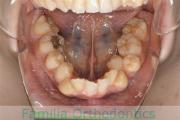

No.23V-478

- 叢生

- 30歳

- 男性

- 抜歯部位

- 上:

- 44済

- 下:

- 8558済

- 主な使用装置:

- FEA 022

- 治療にかかった費用:

- 76万円

右上の歯が重なっているところが邪魔になるとのことで矯正治療を始められた患者さんで、札幌から転院されました。当院で約1年半、15回程度の通院が必要でした。叢生(でこぼこ、凹凸、ガタガタ)が強く、後戻りのリスクが高いケースです。